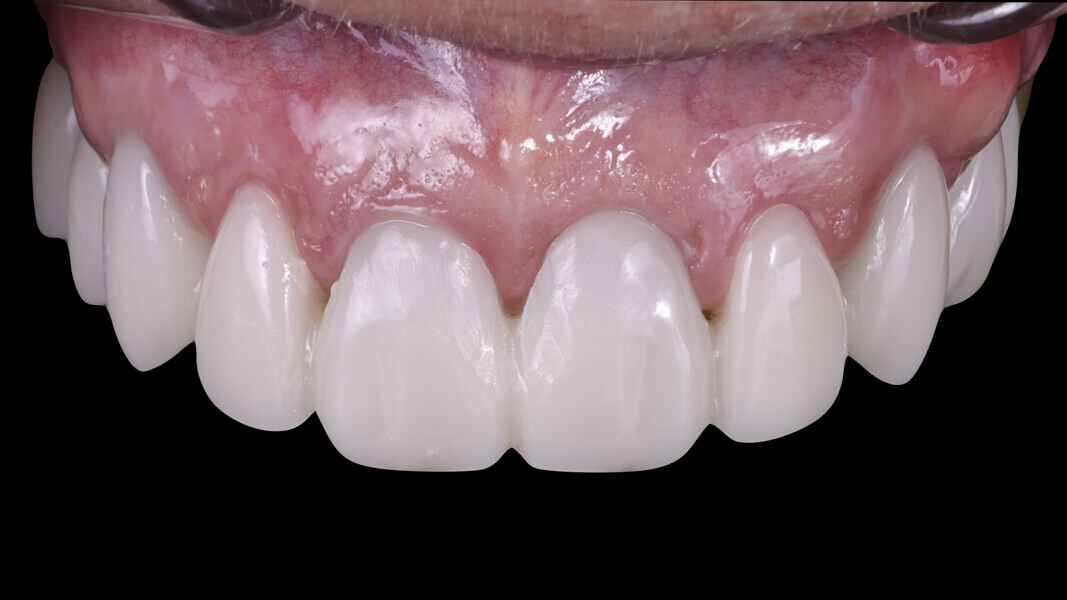

3. Soft-tissue aesthetics and passive fit: The most important aspect in this case was the appearance of the soft tissue. Upon insertion of the definitive restoration, we achieved a perfect result and no blanching of the gingivae, indicating proper tissue support. Furthermore, there was no tension upon insertion, ensuring a comfortable fit and long-term stability of the zirconia restorations (Figs. 33–35).

Figs. 33 & 34: Appearance of the papillae on the day of cementation.

Fig. 35: Definitive restoration in place.

This design strategy, combining precision in planning and soft-tissue management, resulted in a highly aesthetic and functional definitive restoration (Figs. 36a–37b).